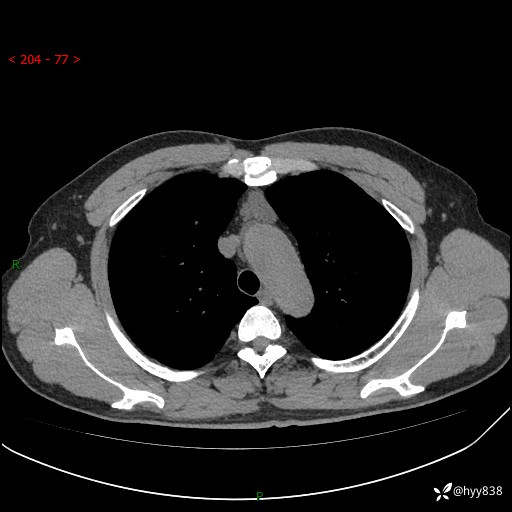

患者性别:女

患者年龄:49岁

简要病史:跟骨骨折,常规CT发现纵隔占位

胸部CT平扫